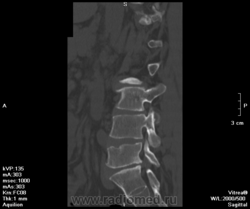

Остеопороз. Спондилодисцит (репоративная стадия?). Спондилоартроз. Деф.спондилоз. Грыжа L IV-V, распространяющаяся на правое межпозвонковое отверстие . Протрузия LV-SI.

1973 г.р. Автослесарь. Жалобы на боли в пояснице и правой ноге. С-реактивного белка в направлении нет, анамнез не описан.

Остеоходроз. Грыжи Шморля. Данных за спондилит и остеопороз не вижу.

У первого пациента грыжа Шморля. Данных за туберкулез я не вижу: контуры замыкательных пластинок четкие, структура окружающей ткани позвонков не нарушена, натечников нет.

Бывает, конечно, что по этому поводу голову ломаешь - деструкция ли это, или только шморлевские узелки. Но здесь все четко.

а что с верхней пластинкой L5? И L4 тоже. откуда такая узурация, особенно в передней части позковнка. неужто шморля?

И где лордоз

Да, узелки Шморля в верхней пластинке. Лордоз выпрямлен, но что это доказывает?

А собственно и ничего. Покалось листез есть небольшой L5, как причина протрузии м.б. Но это, вероятнее, из-за сколиоза.

Расскажите про Шморля. Чтойто они такие. По представленным второй ряд средний скан L3-L4 задний край -вот я так себе их представляю на КТ. В L4, L5, S1 практически вся поверхность съедена, это они подряд так выстраивются? Ведь если одна, то она углублятся будет, а не по горизонтали распространяться. Может уже что другое там? Перенесенное что-нибудь?

Соглашусь, L5, конечно, ненадежно выглядит. Угрожающе.

Ну да, подряд выстраиваются))) Как солдаты.

О причинах этого можно рассуждать долго: может быть, все дело в остеопорозе, может, в нестабильности. Бог знает. Главными дифференциально-диагностическими признаками здесь служат четкость кортикального слоя и отсутствие мягкотканных изменений.